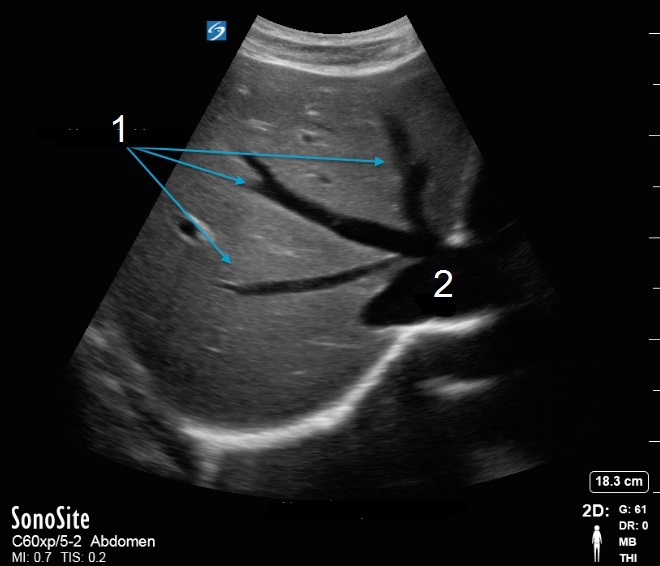

Image : Vue transverse du foie et des veines hépatiques

1. Veines hépatiques

2. Veine cave inférieure (VCI)